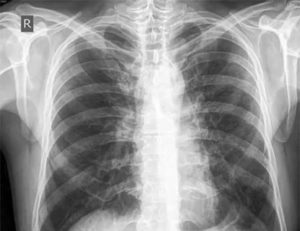

Для визуализации патологического процесса назначается рентгенологическое исследование органов грудной клетки, которое позволяет обнаружить изменения в легких. Обнаруживаются изменения с обеих сторон, преимущественно в нижних отделах легких.

Отмечаются усиление и деформация легочного рисунка, постепенно формируется картина так называемого «сотового легкого», которое характеризуется образованием кольцевых теней диаметром 3 – 7 мм со стенками толщиной до 3 мм, что в некоторой мере напоминает пчелиные соты.